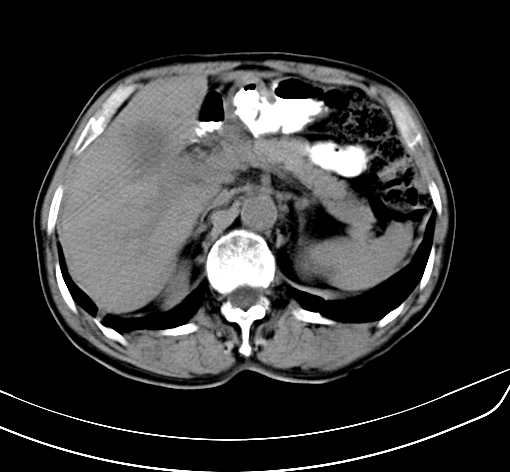

病人 男 70 咳嗽 胃部不适 2月余

胆囊壁增厚,与临近肝实质边界不清,临近肝实质内可见大片边界不清之低密度区,肝门区密度亦有减低,部分结构不清,尾叶前方可见块状影,肝右叶可见多枚边界不清之圆形低密度区,肝内胆管扩张征象,结合病史考虑1胆囊癌肝内转移,肝门区淋巴结转移,门脉癌栓待排2肝内胆管扩张3建议增强扫描

肝脏多发大小不等低密度灶,边界不清,肝门区结构不清,肝内胆管轻度扩张,胆囊密度不均匀,内见软组织样密度影,与相临肝脏边界不清.考虑:1、胆囊ca侵犯肝脏并肝内多发转移,肺上也有结节影,转移?建议强化扫描.2、胃充盈不好,如怀疑有病变最好建议做相关检查.

胆囊壁增厚,周围模糊不清,肝内多发低密度影,胃充盈欠佳,胃壁增厚,外形尚规整,考虑胆囊炎、胆囊癌肝内转移?建议胃肠道进一步检查或增强扫描。